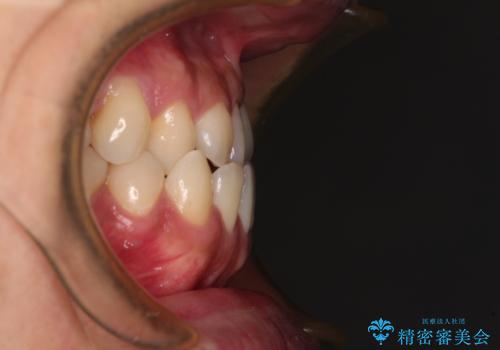

- 前歯のクロスバイトを気にして来院された患者様です。

1年半後に結婚式が控えているとのことで、ワイヤー矯正で早めに治療を終えることを希望されました。

骨格的に下顎が前方に位置していましたが、歯列矯正で改善できると判断し、ワイヤー装置にて矯正治療を行うこととしました。